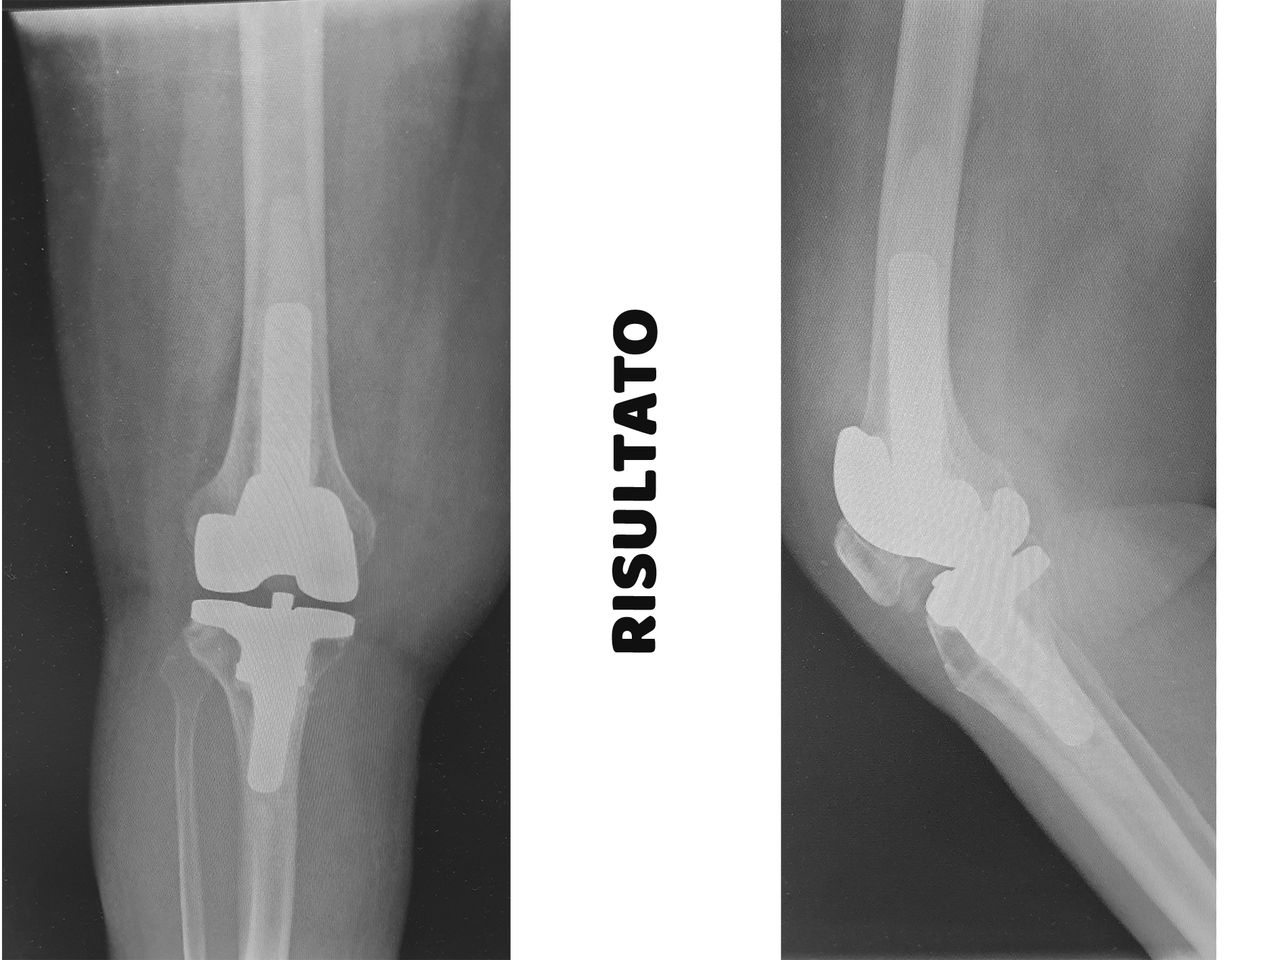

* Protesi Totali di Ginocchio, (ANALLERGICHE in Oxinium)

* Protesi Mono-Compartimentali di Ginocchio (ANALLERGICHE in Oxinium)